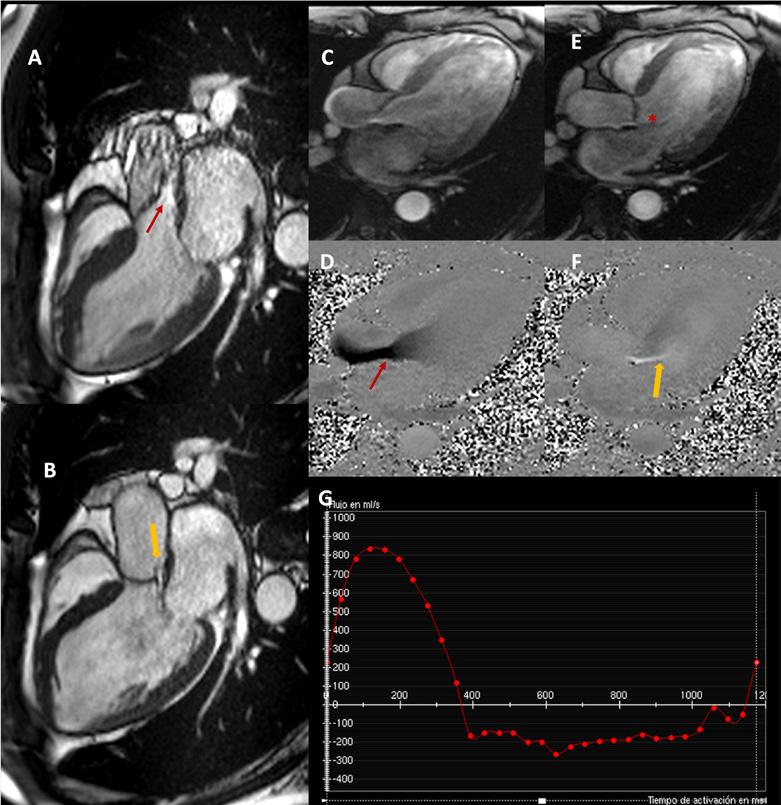

Masculino de 55 años con diagnósticos de coartación aórtica y aorta bivalva. En la infancia fue llevado a reparación quirúrgica de la coartación (coartectomía) y continuó valoración médica sin síntomas cardiovasculares. En los últimos 2 años aqueja de dificultad para respirar al realizar actividades de moderada a gran intensidad, por lo que su médico tratante solicita una angiotomografía de arterias coronarias y de aorta torácica en búsqueda de recoartación. En dicho estudio se encontró como datos relevantes la presencia de aorta bivalva de tipo Sievers I (con 1 rafe en las valvas fusionadas), con calcificación leve y restricción al cierre (lo que se conoce como insuficiencia valvular) grave además de una imagen sugerente de ruptura de una de las valvas; dilatación de las cavidades izquierdas del corazón (aurícula y ventrículo izquierdos), enfermedad ateroesclerosa en las arterias coronarias con mínima obstrucción, y sin datos de recoartación en la aorta reparada. (Figuras 1 y 2) Se complementa el abordaje con resonancia magnética cardíaca (RMC) para caracterizar la válvula aórtica, cuantificar la gravedad de la insuficiencia valvular aórtica y buscar alguna obstrucción en la aorta ya reparada. La RMC corrobora la dilatación del ventrículo izquierdo con

presencia de insuficiencia grave (fracción regurgitante de 56%) excéntrica sin ruptura de la valva aórtica y sin obstrucción en istmo aórtico (Figura 3).

Figura 1: Imágenes de reconstrucción multiplanar multifásica mostrando válvula aórtica bivalva tipo I de Sievers (1 rafe no calcificado) con máxima apertura valvular por planimetría (4 cm2) en sístole (A) y orificio regurgitante excéntrico en diástole de 0.35 cm2(B).

Figura 2: Imágenes de reconstrucción volumétrica del árbol coronario (A y B) mostrando origen normal de arterias coronarias y dominancia izquierda. En C, reconstrucción angiográfica de aorta torácica y abdominal, observándose istmo (flecha roja) con mínima reducción de su diámetro (no cumple criterios para re-coartación), sin circulación colateral y origen normal de vasos supra-aórticos.

Figura 3: Imágenes de cine por RMC mostrando aceleración en sístole (flecha roja) a través de una válvula con apertura excéntrica (A) y en diástole (B) el flujo regurgitante por prolapso (flecha amarilla) comprometiendo la apertura de la valva anterior de la mitral. Dichos hallazgos son evidentes en secuencia de contraste de fase (D, F) apreciándose el flujo excéntrico (flecha amarilla) que contacta con valva anterior de la mitral (E, asterisco). En G se presenta la curva de cuantificación del volumen anterográdo (221 mL) y retrógrado (124 mL) que atraviesa (secuencia trough-plane) la válvula aórtica con una fracción regurgitante calculada de 56%, considerándose insuficiencia grave.